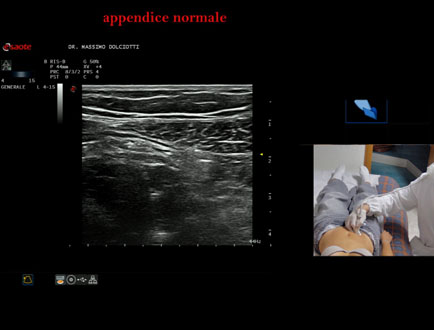

Data inserimento: 26/09/2025

Ecografia del: 12/09/2025

Strumento: Esaote MyLab Eight

Sonda: Lineare Multifrequenza 4-15 MHz

Età Paziente: F 24 anni

Motivazione dell'esame: da 3 mesi dolore al fianco destro.

Commento all'esame: le immagini ed il video documentano l'appendice di spessore normale (5,1-5,7 mm - v.n. < 6 mm).

Conclusioni: appendice normale (normal appendix).

Presentazione: Dr. Massimo Dolciotti - Ancona

Elaborazione digitale: Andrea Dini - Ancona